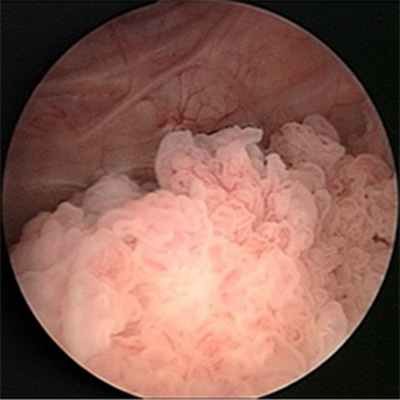

Ведущим методом диагностики рака мочевого пузыря является цистоскопия. Метод заключается в осмотре полости мочевого пузыря. При цистоскопии можно оценить состояние слизистой мочевого пузыря, размеры, количество, локализацию, внешний вид, распространенность опухоли, а также вовлеченность устьев мочеточников.

- Эндоскопия позволяет визуально обнаружить внешний вид неоплазии, её размер и локацию. К тому же это обследование даёт возможность взять биопсию и осуществить морфологическое подтверждение рака мочевого пузыря.

На сегодняшний день основной метод диагностики опухоли мочевого пузыря – цистоскопия (осмотр слизистой мочевого пузыря «изнутри» с помощью специального прибора - эндоскопа), позволяющая не только увидеть опухоль, но и взять кусочек новообразования для гистологического исследования. Основной недостаток данного метода, сильно ограничивающий его применение, – известная инвазивность (дискомфорт для пациента).